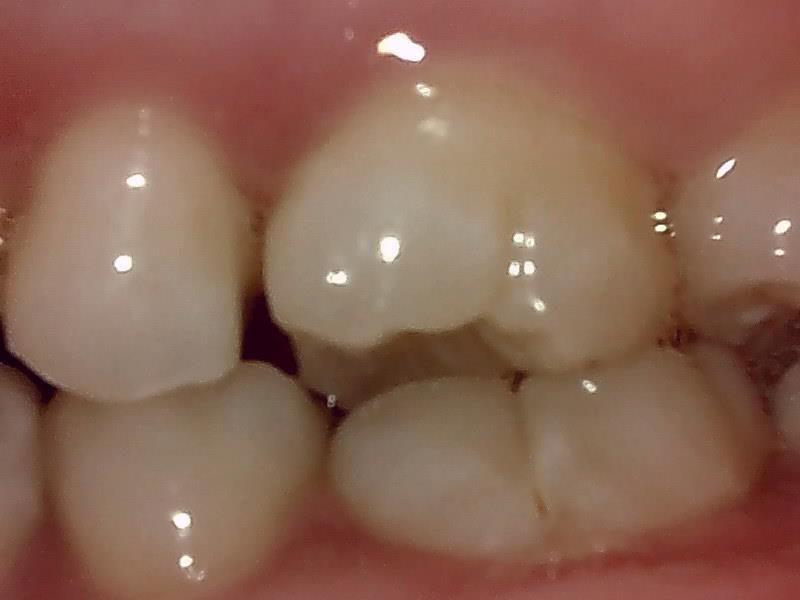

左側

右側